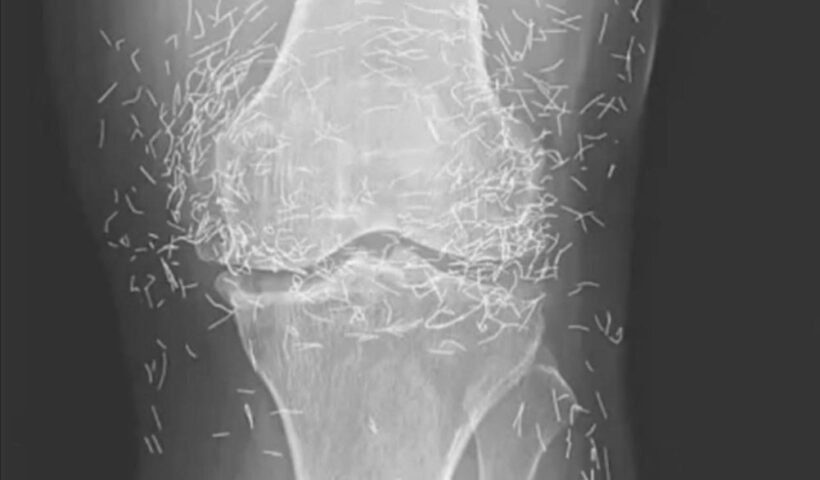

View More Keep bathroom light on when sleeping in hotel – Here’s whyWhen a 65-year-old South Korean woman went in for knee pain, doctors weren’t expecting to strike gold. But that’s exactly what they found. Unwanted stomach…

View More A 65-year-old woman came to the clinic after experiencing months of chronic knee pain. Despite trying multiple treatments including traditional Chinese medicine she found no relief. This X-ray was taken during her visit. What do you think is the diagnosis. Answer in the commentsChia seeds have become a staple in the world of nutrition thanks to their numerous health benefits. Easy to incorporate into many recipes, they are…